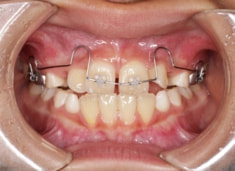

治療法:上顎急速拡大装置+クリアスナップ+フェイスマスク+上顎3番は開窓牽引CT写真にて位置確認

(難症例のため、小児期の矯正を2段階に設定しました)